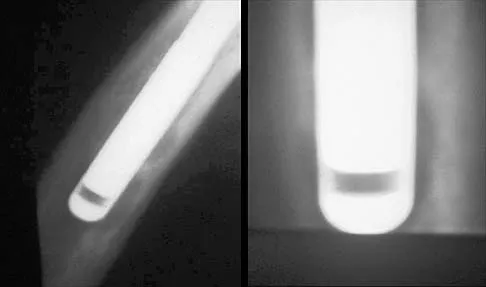

A 5-year-old boy sustained an elbow injury. Examination in the emergency department reveals that he is unable to flex the interphalangeal joint of his thumb and the distal interphalangeal joint of his index finger. The radial pulse is palpable at the wrist, and sensation is normal throughout the hand. Radiographs are shown in Figures 6a and 6b. In addition to reduction and pinning of the fracture, initial treatment should include

The findings are consistent with a neurapraxia of the anterior interosseous branch of the median nerve. This is the most common nerve palsy seen with supracondylar humerus fractures, followed closely by radial nerve palsy. Nearly all cases of neurapraxia following supracondylar humerus fractures resolve spontaneously, and therefore, further diagnostic studies and surgery are not indicated. Cramer KE, Green NE, Devito DP: Incidence of anterior interosseous nerve palsy in supracondylar humerus fractures in children. J Pediatr Orthop 1993;13:502-505.